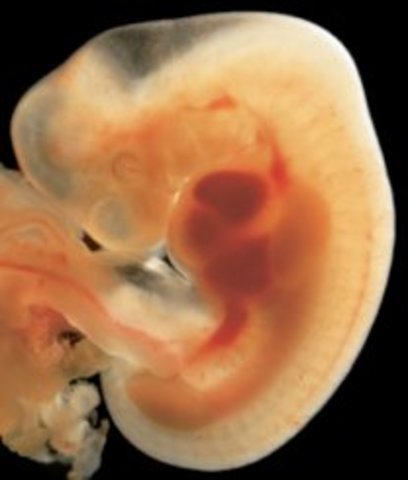

• week 2 fertilization

week 2 fertilization

this is when the sperm cell successfully penetrates the egg in the fallopian tube, and the egg does not allow any more sperm to enter. Then the cells start dividing really quickly and will keep doing so until the fetus develops all anatomical structures.

Facts: in order to develop twins the egg has to split into two

• week 3 Life

week 3 Life

The egg will continue to divide and travel down the fallopian tube where it will eventually end up in the uterus. The sex of the child is already embedded in the DNA of the sperm,so when the egg is fertalized it already carries all of its genetic code.